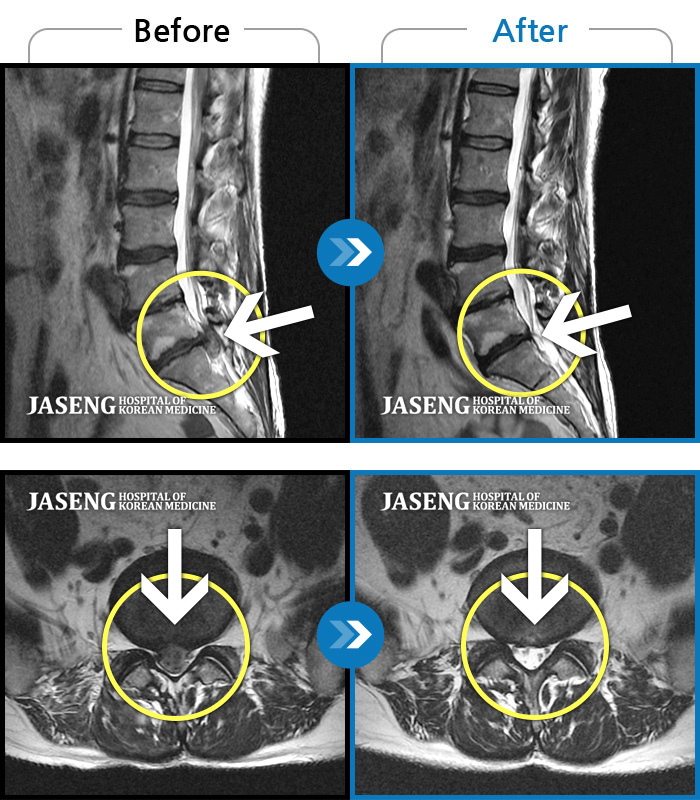

[뱸] 19.11.28~25.05.06

ȯںп Ǹ ǿ ԿǾ, ο ġ ۿ Ƿ ġḦ Ͻñ ٶϴ.